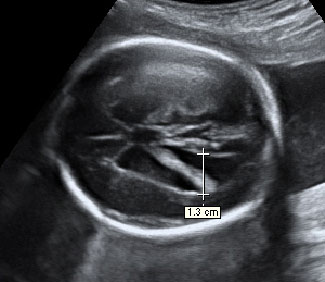

En la ecografía en 2D de la semana 20 de embarazo se hace un estudio pormenorizado de los órganos internos del feto y de su anatomía. Así se descubren muchas malformaciones congénitas, como en este caso, un pie equinovaro o zambo.